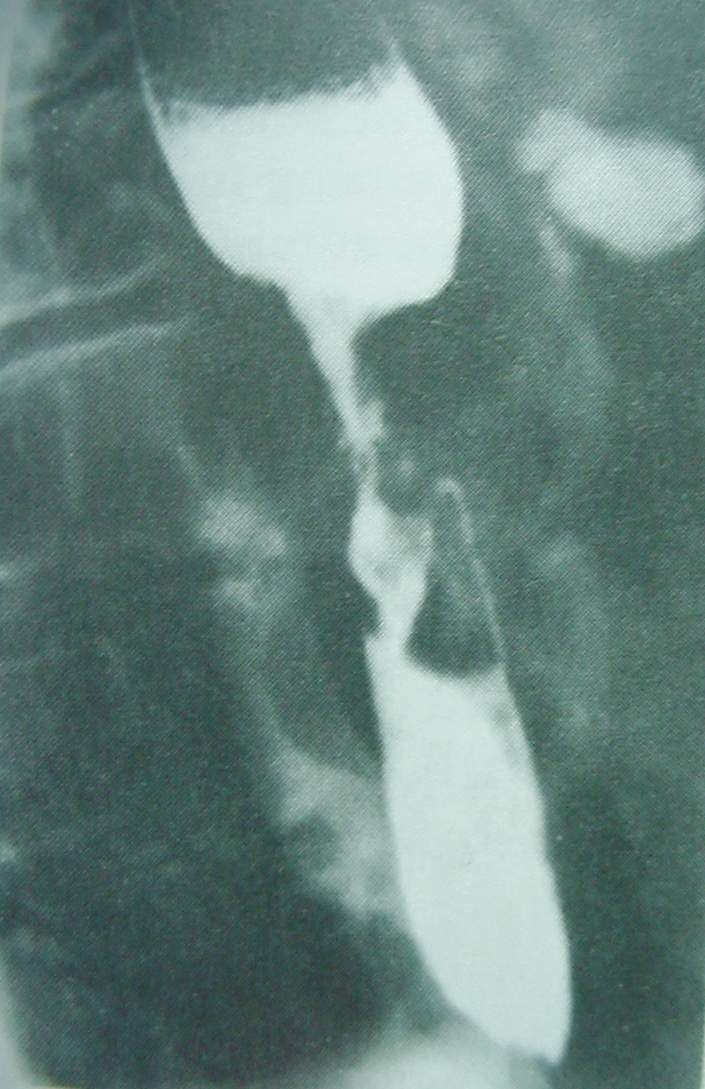

Pharynx and Esophagus Clinical Photos for Static Stations